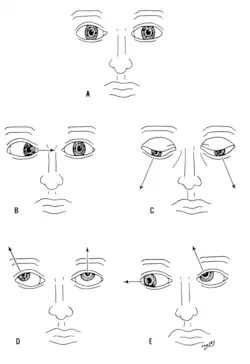

De nervus oculomotorius (N. III), nervus trochlearis (N. IV) en nervus abducens (N. VI) sturen samen oogbewegingen aan.

Schade aan nervi III, IV en VI kan de beweging van de oogbal aantasten. Eén of beide ogen kunnen worden aangetast, maar in beide gevallen treedt waarschijnlijk dubbelzien (diplopie) op omdat de bewegingen van de ogen niet meer synchroon zijn. Nervi III, IV en VI worden getest door te kijken hoe het oog een object, zoals een vinger, volgt op verschillende plekken. Het object kan in verschillende richtingen worden bewogen om ook de achtervolgingssnelheid te testen.[3] Als de ogen niet samenwerken, komt dit hoogstwaarschijnlijk door schade aan een specifieke hersenzenuw of de bijbehorende nuclei.[3]

Schade aan de nervus oculomotorius (N. III) kan leiden tot dubbelzien en tot een onvermogen om de bewegingen van beide ogen te coördineren (strabisme). Ook kan het leiden tot het afhangen van één of beide oogleden (ptose) en pupilverwijding (mydriase).[11] Verder kunnen laesies leiden tot het onvermogen om het oog te openen, doordat de musculus levator palpebrae superioris verlamd is geraakt. Soms compenseren mensen die een laesie hebben aan N. III voor hun symptomen door het hoofd te draaien.[3]

Een beschadigde nervus trochlearis (N. IV) kan ook leiden tot diplopie.[11] Het resultaat is een oog dat niet meer goed naar beneden kan bewegen, vooral wanneer het zich in een inwaartse positie bevindt. Dit komt doordat de bovenste schuine oogspier beperkt wordt, omdat deze wordt aangestuurd door N. IV.[3]

Ook schade aan de nervus abducens (N. VI) kan leiden tot diplopie.[11] Dit komt doordat de zijdelingse rechte oogspier wordt aangestuurd door N. VI.[3]